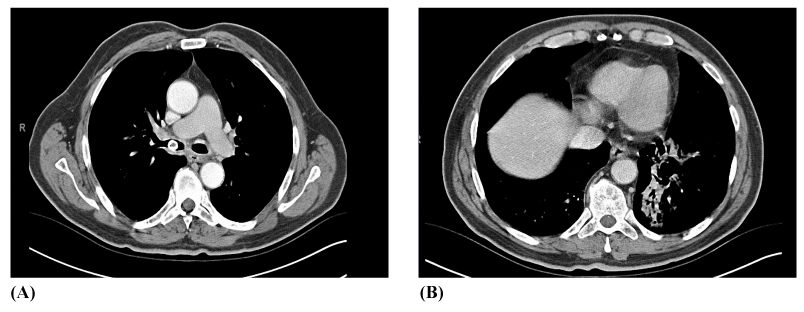

Blood tests done showed a mild leukocytosis (17300IU/mL); renal and hepatic panels were normal. Arterial blood gas analyses were also normal. His chest radiograph showed no abnormality, except a suspicious heterogenic density behind the left heart silhouette. CT scans of the thorax are shown below in Figure 1A and Figure 1B. Bronchoscopy was then performed, which showed a polyploidy lesion on the posterior wall of the left main bronchus, whereas an oval shaped mobile body was observed over the right main bronchus, under the right upper lobe division (Figure 2A) (Figure 2B). The pathological diagnosis of the specimen taken from the polypoid lesion was compatible with active chronic granulation.

Figure 1 A) CT scans of the case demonstrating a foreign body in the right main bronchus. B) Consolidation in left lower lobe.